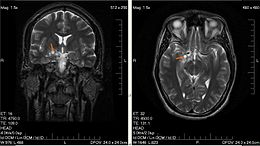

据海外医疗服务机构厚朴方舟了解,UCLA的研究人员发现将UCLA开发的一种疫苗与其他实验性治疗方法及FDA批准的治疗方法联合在一起可以减小晚期脑胶质瘤的大小。这种特异性靶向脑胶质瘤的免疫治疗方法方法方法叫做自体肿瘤裂解液激活的树突状细胞疫苗(DCV)。这种治疗方法使用了病人的一部分脑部肿瘤组织,目前正在人体身上进行试验。

在动物实验中,研究人员发现将DCV与两种调节免疫系统不同方面的药物联合在一起使用可以让T细胞更有效进攻脑胶质瘤细胞。这两种额外的药物分别是一个PD-1抗体(促进肿瘤内的T细胞激活)和一个叫做PLX3397的实验性药物(可以减弱肿瘤内的免疫抑制效应)。

脑胶质瘤是成年人中较常见的一种恶性脑部肿瘤之一,也是致死率较高的一种恶性肿瘤。据估计今年将有12000人被诊断出患有胶质瘤,而令人痛心的是这些病人的五年生存率低于5%。同时,这种癌症复发的可能性很高,但是目前还没有针对复发肿瘤的标准治疗方法。研究人员在小鼠及肿瘤病人的肿瘤组织中进行了研究。